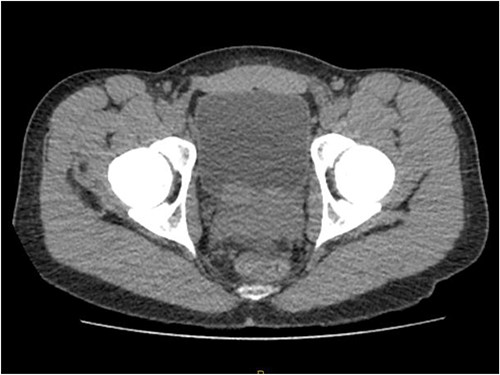

Laboratory tests of full blood count and liver function test were unremarkable with prostate specific antigen of 0.53. Mid-stream urine MCS did not show any infection and urine cytology was negative. Renal function test revealed progressive worsening of previously normal eGFR down to 27 ml/min. Initial renal tract ultrasound (Fig. 1) showed enlarged prostate indenting into the bladder base with high post micturition urine residual volume of 185 ml but no hydronephrosis. CT KUB (Fig. 2) showed irregularly enlarged prostate with bilateral hydroureteronephrosis. MRI prostate showed enlarged prostate with PIRADS 5 amorphous mass suspicious for carcinoma involving bilateral seminal vesicles and right vesicouretric bladder. FDG PET (Fig. 3) showed unusual distribution pattern of lymphoma involving the prostate with bilateral symmetrical renal, early pulmonary, and possibly right thyroid lobe involvement.

Renal ultrasound showing enlarged prostate indenting into the bladder.